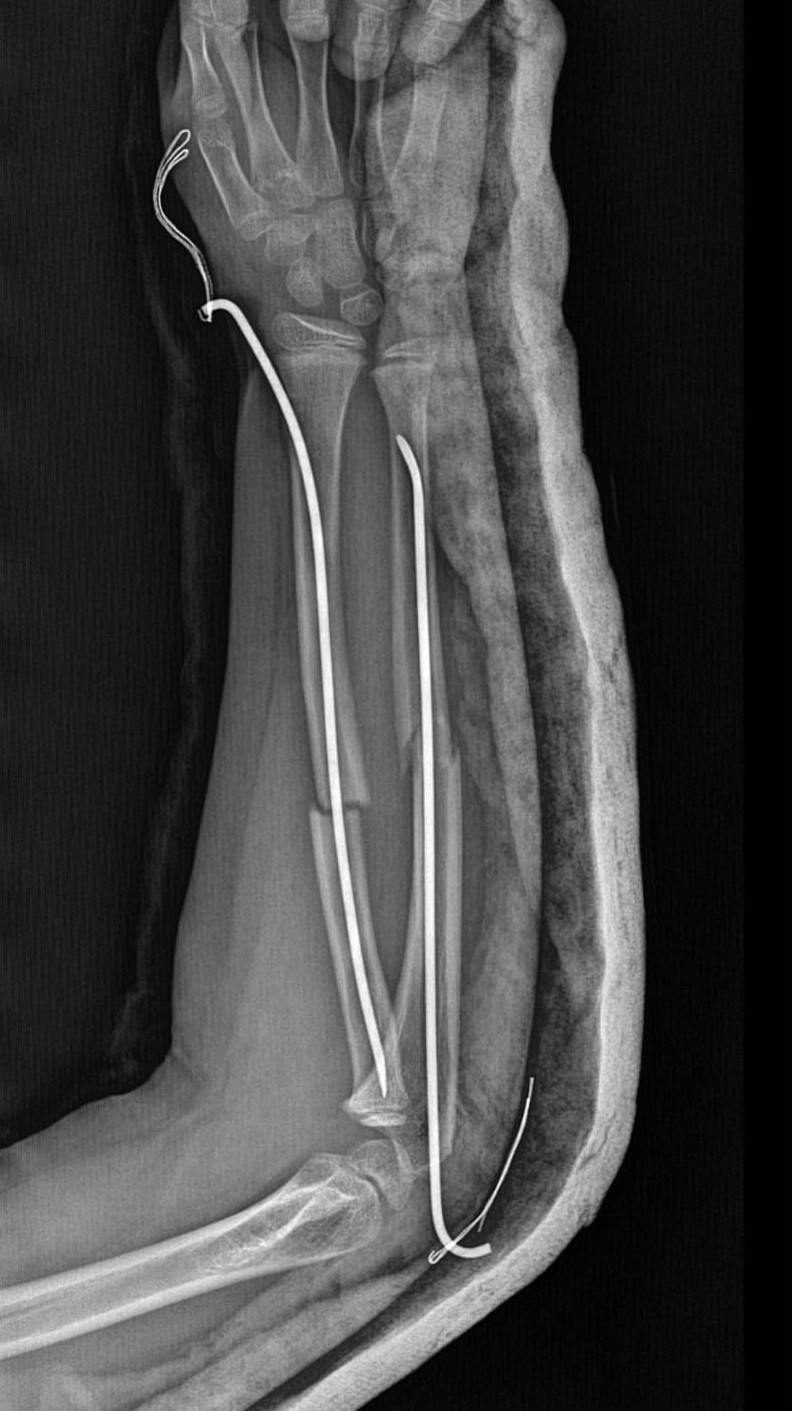

Olay, geçtiğimiz ay Büyükçekmece Tepecik'te bulunan bir ilkokulda meydana geldi. İddiaya göre 8 yaşındaki Y.K.Ş. okulda bir süredir kendisini rahatsız eden 9 yaşındaki çocuk tarafından darp edilerek kolu ikiye katlandı. Y.K.Ş.'nin 2'ye katlanan kolu 2 ayrı yerinden kırıldı. Öğretmenler Y.K.Ş.'nin ailesini arayarak, ‘oğlunuz arkadaşıyla kavga etti duvara çarptı' denildi. Oğlunu okuldan alıp hastaneye götüren anne Songül Gökdemir, oğlunun kolunun 2 ayrı yerinden kırıldığını öğrenip ameliyata alınacağını duyduğunda büyük şok yaşadı. Konuyla ilgili anne Gökdemir savcılığa giderek şikayetçi oldu. Savcılıktan ise 'söz konusu Suça Sürüklenen Çocuğun yaşının 12'den küçük olduğu gerekçesi ile kovuşturmaya yer yoktur' kararı çıktı. Anne Gökdemir karara itiraz ederken mağdur Y.K.Ş. ise haftalardır okula gidemiyor. Eğitimi aksayan çocuğun 2 hafta sonra ise platinlerinin çıkarılması için yeniden ameliyata gireceği öğrenildi.

Yaşanan olayı anlatan Songül Gökdemir, " Arkadaşlarından darbe aldığını biliyordum. Ayrıca Eylül ayından bu yana bir arkadaşının onun kolunu kırmaya çalıştığını söyledi. Ben de 'arkadaşını öğretmene söyle' dedim. Bundan kaçıyordu. O gün de rehber öğretmenine bu arkadaşını şikayet ettiler. Ben işe gittim 1 saat sonra öğretmeni aradı. Oğlunuz arkadaşıyla birbirini itekledi kolunu duvara çarptı gelir misiniz ?' dedi. Kendi imkanımla hastaneye götürdüm. Okula gittiğimde de oğlum derste oturuyordu. Öğretmen ders işliyordu ambulans çağırılmamış. Hastanede kolunda 2 tane kırık olduğunu acilen de ameliyata girmesi gerektiğini öğrendim. 3 gün sonra ameliyata alındı. Kolundaki platinlerden dolayı her gün pansumanı var. 2 hafta sonra tekrar ameliyatı var" dedi.